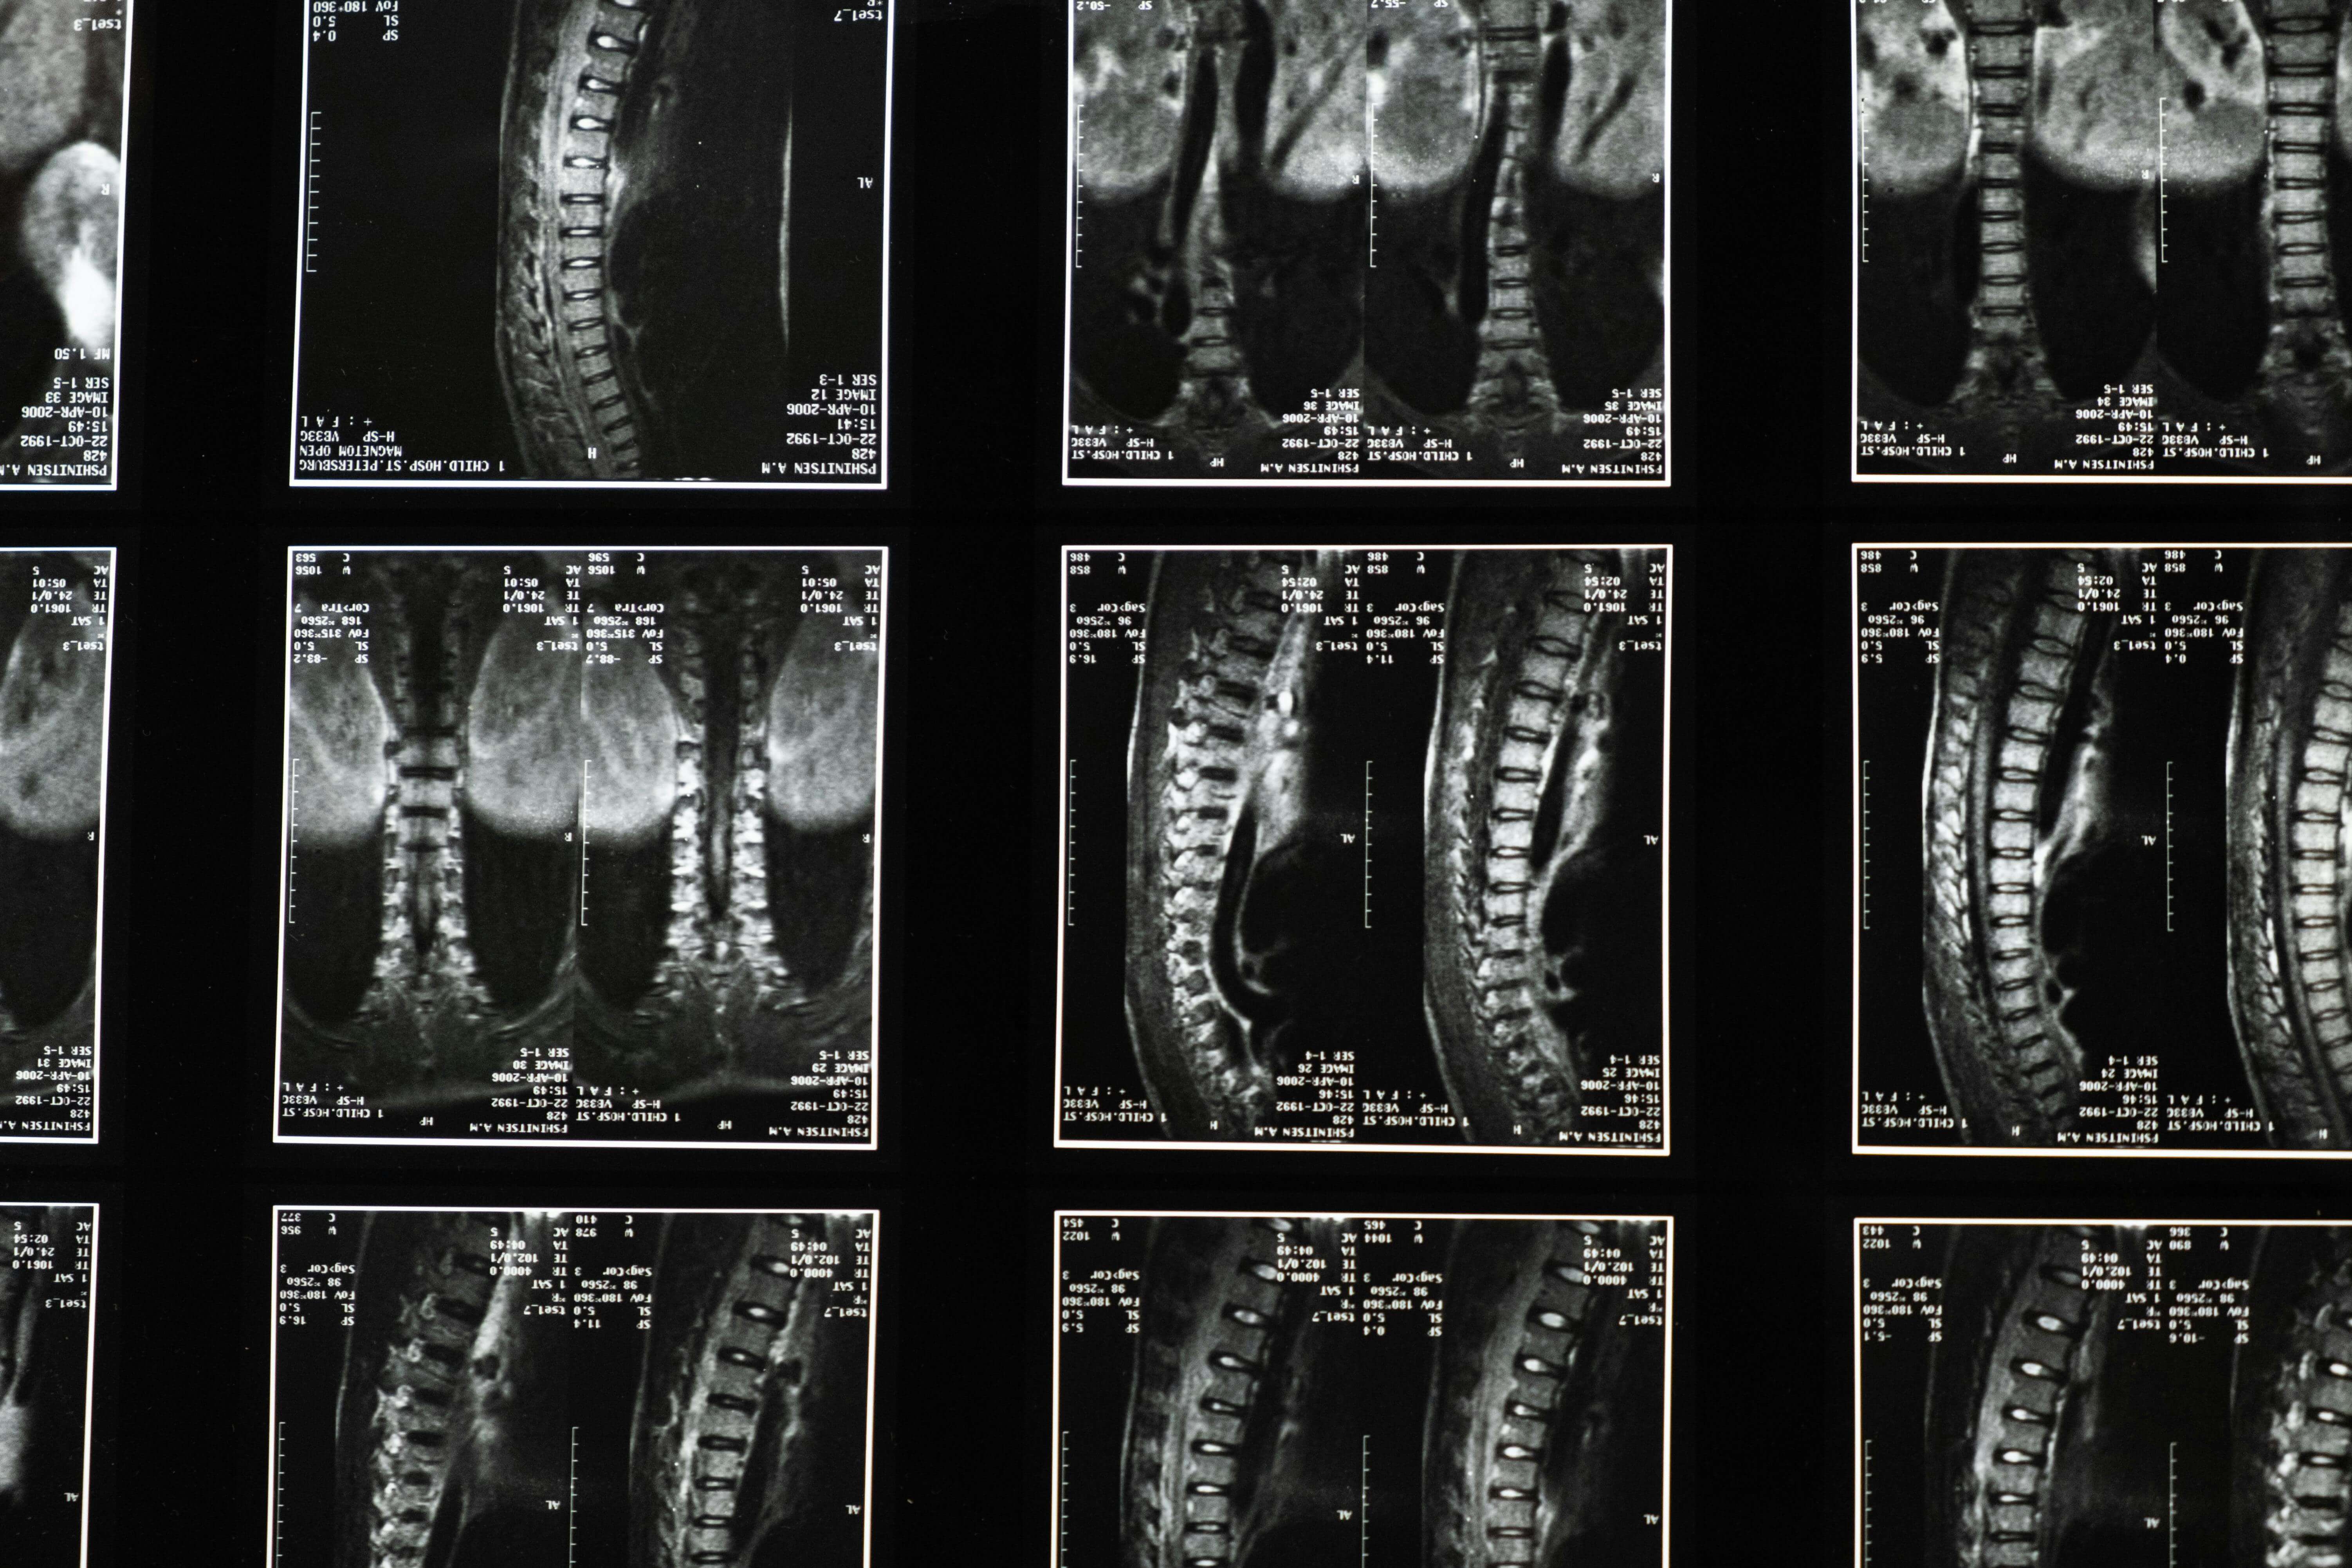

저도 어렸을 때 방방에서 점프하다가 목 부분에 충격을 받은 적이 있습니다. 그때 잠깐이나마 숨도 못 쉬고 온몸이 움직이지 않던 순간의 공포는 지금도 생생합니다. 지금 건강운동관리사를 공부하면서 돌아보니, 그건 정말 아찔한 순간이었다는 걸 깨달았습니다. 척수는 우리 몸의 중추신경계 중심부로, 뇌와 신체 각 부위를 연결하는 신경 전달의 핵심 통로입니다. 척수손상(SCI)은 손상 부위 이하의 운동·감각·자율신경 기능을 모두 잃게 만들 수 있으며, 요추(L2~S2) 손상 시 방광과 장 조절 능력 상실, 경추(C4~C8) 손상 시 사지마비나 호흡 보조 필요 등 삶 전체를 바꿔놓는 심각한 결과를 초래합니다.

일반적으로 척수손상이라고 하면 '마비'만 떠올리는 분들이 많은데, 제 경험상 더 무서운 건 자율신경계의 혼란입니다. 척수 손상 위치에 따라 우리 몸의 자율신경 조절 능력이 완전히 무너질 수 있습니다. 특히 T6(흉추 6번) 이상 손상 환자의 경우 자율신경반사부전증(Autonomic Dysreflexia, AD)이라는 생명을 위협하는 응급 상황에 직면할 수 있습니다.

여기서 자율신경반사부전증이란 척수 손상 부위 아래에서 발생한 자극(방광 팽만, 장 팽창 등)에 대해 척수가 뇌의 조절 없이 과도하게 반응하는 현상을 의미합니다. 갑작스러운 혈압 상승(수축기 혈압 200mmHg 이상), 심한 두통, 서맥, 땀 분비 이상, 피부 발적 등이 나타나며 뇌졸중이나 심근경색으로 이어질 수 있습니다. 출처: (대한재활의학회)